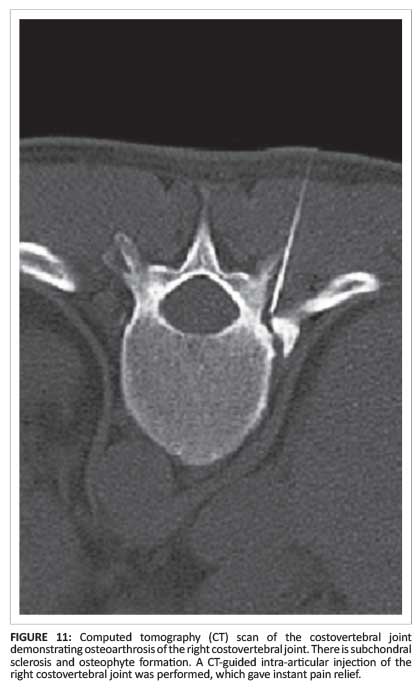

CT-guided injections to the costovertebral and thoracic facet joints are administered to expedite return to activity (Figure 11).